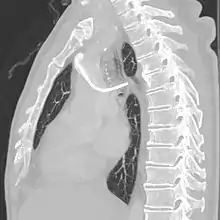

A port consists of a reservoir compartment (the portal) that has a silicone bubble for needle insertion (the septum), with an attached plastic tube (the catheter). The device is surgically inserted under the skin in the upper chest or in the arm and appears as a bump under the skin. It requires no special maintenance other than occasional flushing to keep clear. It is completely internal so swimming and bathing are not a problem. The catheter runs from the portal and is surgically inserted into a vein (usually the jugular vein or less optimally the subclavian vein). Ideally, the catheter terminates in the superior vena cava or the right atrium. This position allows infused agents to be spread throughout the body quickly and efficiently.

The port is then sutured on two sites to the underlying muscles. The tip of the catheter is checked for kinks and position using a fluoroscope. Besides that, aspiration of blood and contrast injection through the chemoport can also be used to confirm the position. The port is the closed in two layers (subcutaneous tissue is sutured first, followed by the skin). Sterile dressing is then placed on the port.[3] The optimum site to park the tip of the catheter is at the cavo-atrial junction or with margin of error of not more than 4 cm above the junction.[3]

A follow-up on a chest radiograph can immediately detect complications associated with the procedure such as pneumothorax, hemothorax and malpositions of the catheter. However, routine chest radiography is not needed due to the low complication rates associated with the procedure. The chest radiograph is only done if there is clinical suspicion of a complication.[4]

The incidence of catheter fracture is 2.3%. The fracture can be due to "pinch-off syndrome" when the vein and the catheter is compressed when passes between the clavicle and first rib before turning 90 degrees into the superior vena cava. Fractured catheter component can dislodge most commonly into pulmonary arteries (35%), right atrium (27%), right ventricle (22%), and superior vena cava and peripheral veins (15.4%).[5]

Malpositioning of the catheter happens in 0.1 to 5.6% of the time. This can be due to malposition within or outside the superior vena cava. Causes includes: unexpected branches of the veins, vessel angulations, vein stenosis or venous tortousity.[5]